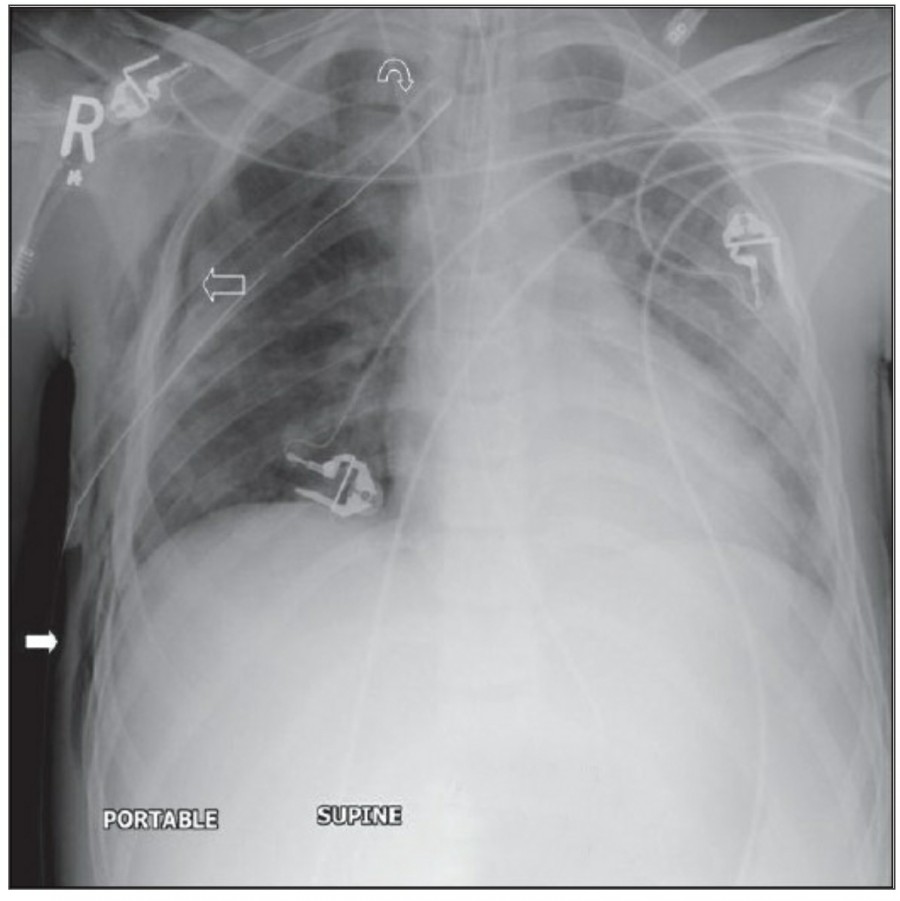

중환자에서 pneumothorax의 진단은 종종 supine radiograph에서 내릴 수 있다. Supine position에서 공기는 anteromedial 방향으로 모이게 되는데, apical air collection이 있을 경우 large pneumothorax가 있음을 시사한다. 공기는 lung과 diaphragm 사이의 subpulmonic location에 trap 되어 있을 수도 있다. 공기가 costophrenic sulcus로 anterolateral extension 될 경우, 이 costophrenic sulcus의 radiolucency를 증가시키는데, 이를 deep sulcus sign이라고 한다. Subpulmonic pneumothorax의 다른 특징으로 diaphragm의 superior surface와 IVC 윗부분이 뚜렷하게 보일 수 있다.

중환자에서 tension pneumothorax의 진단은 매우 힘들다. ARDS와 같은 lung의 병리적인 기전이 lung compliance를 감소시킴으로써 total lumg collapse를 막는다. 또한 tension pneumothorax의 특징인 mediastinal shift가 PEEP으로 인해 나타나지 않을 수 있다. Chest X ray 상에서 tension pneumothorax는 hemidiaphragm의 depression이나 heart border, SVC, IVC의 이동으로 나타날 수 있다.